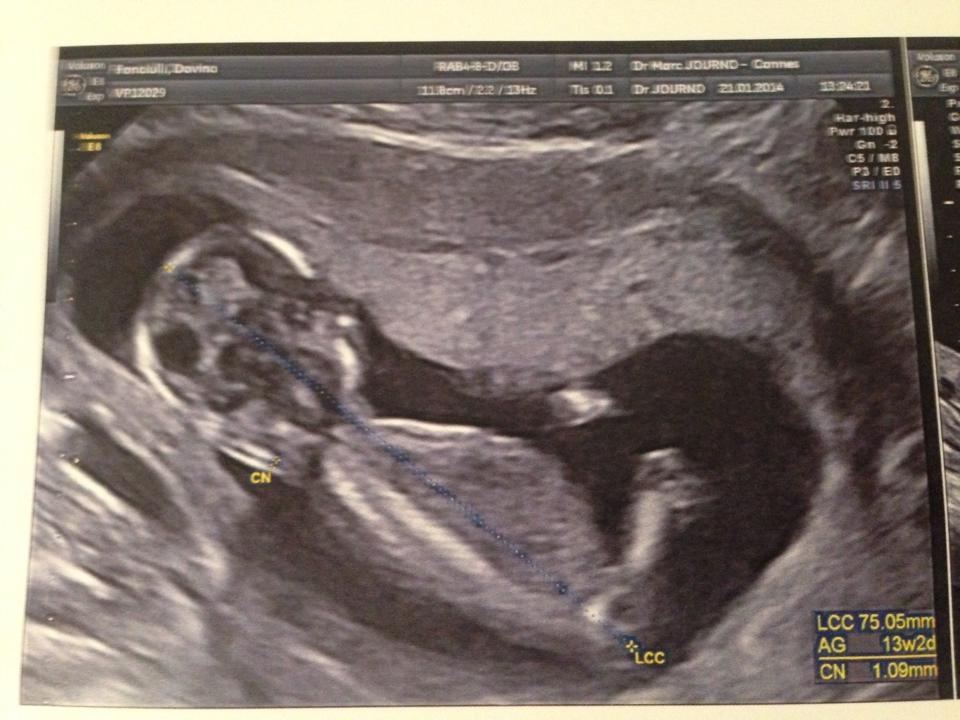

merci pour elle !! et en plus j avais raison sa gygy la premiere disait qu elle etait enceinte depuis le 25/10 .... et moi j avais recalculer ...c etait le 03/11 ... et bah paff j ai raison vu l echo elle a son terme le 03/08/2014.... une petite lionne pour accompagner sa tigresse de grand-mère ....

Pièces jointes

• babychouette.jpg

babychouette.jpg

117.4 KB · Affichages: 138